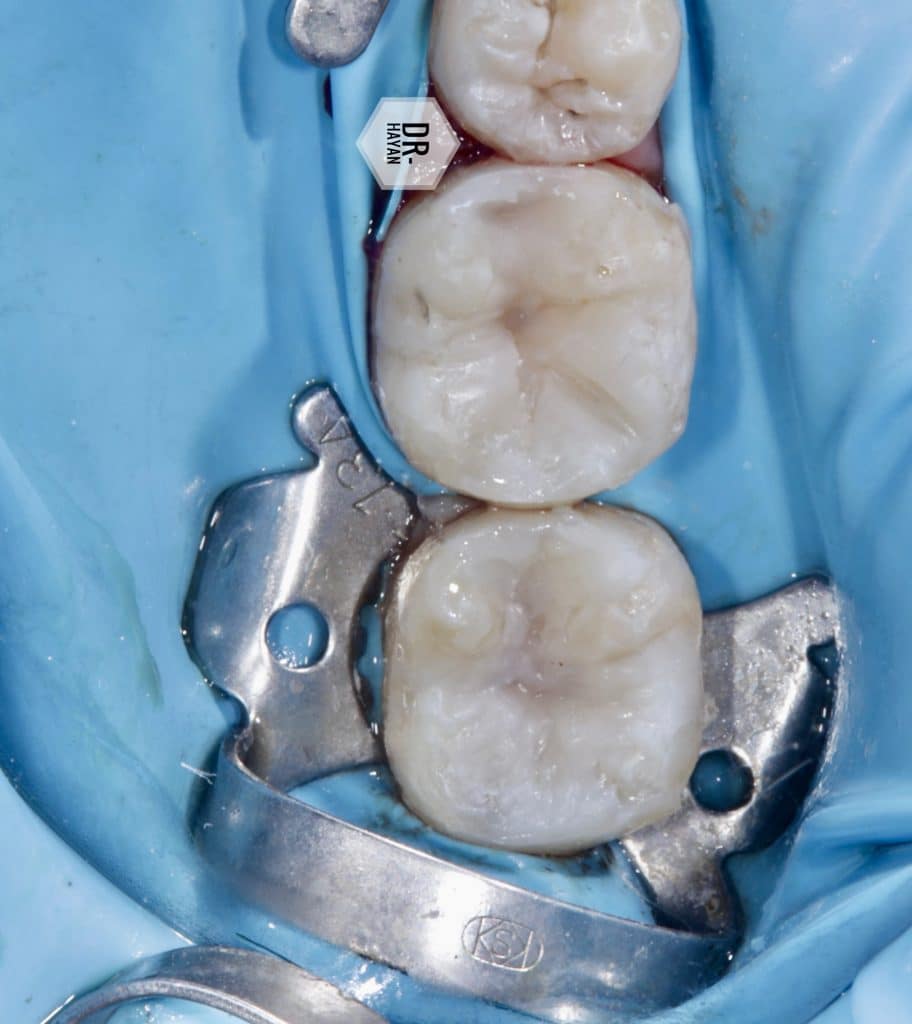

After isolation & split dam between 6 ,5

Remove all old defective filling

And reduction the weakness cusp as distal cusp in 6

Finishing the line angle and floor